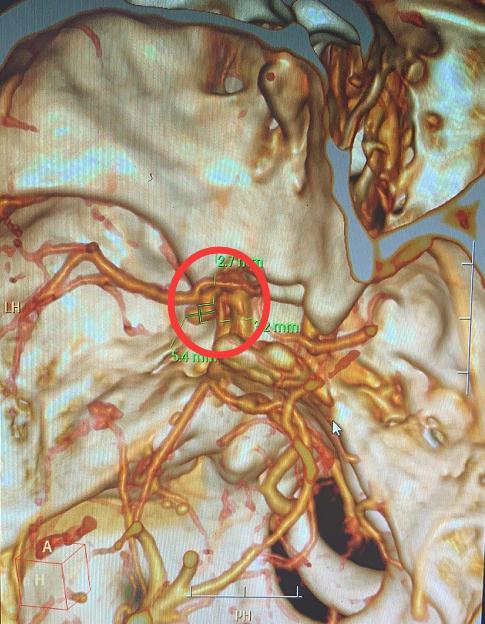

“可能是颅内出血了 。 ”该院接诊的神经外一科主任张良猜测 。 最终相关检查证实 , 患者颅内左侧后交通动脉瘤破裂出血 。

文章插图

患者动脉瘤所在位置

完善相关检查后 , 张良团队紧急为患者实施了动脉瘤夹闭术 , 顺利将破裂出血的动脉瘤“夹住” 。 给予控制血压、预防血管痉挛、抗癫痫等对症治疗后 , 王姐于近日顺利出院 。